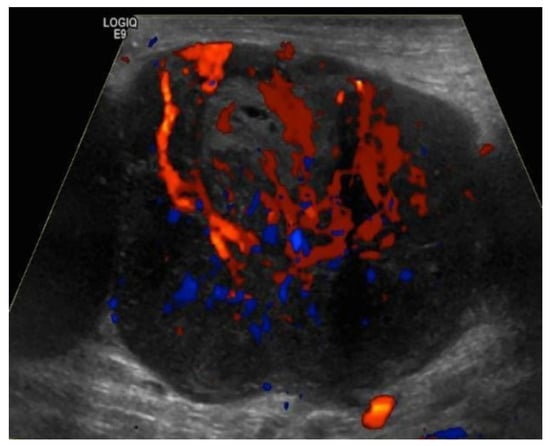

4.1.1. Ultrasound Evaluation of the Lymphatic System

- Prativadi, R.; Dahiya, N.; Kamaya, A.; Bhatt, S. Chapter 5 Ultrasound Characteristics of Benign vs Malignant Cervical Lymph Nodes. Semin. Ultrasound CT MRI 2017, 38, 506–515. [Google Scholar] [CrossRef]

- Wang, B.; Zhang, M.K.; Zhou, M.P.; Liu, Y.; Li, N.; Liu, G.; Wang, Z.L. Logistic Regression Analysis of Conventional Ultrasound, and Contrast-Enhanced Ultrasound Characteristics. J. Ultrasound Med. 2021. [Google Scholar] [CrossRef]

- Dudea, S.M.; Lenghel, M.; Botar-Jid, C.; Vasilescu, D.; Duma, M. Ultrasonography of superficial lymph nodes: Benign vs. malignant. Med. Ultrason. 2012, 14, 294–306. [Google Scholar]

- Vassallo, P.; Wernecke, K.; Roos, N.; E Peters, P. Differentiation of benign from malignant superficial lymphadenopathy: The role of high-resolution US. Radiology 1992, 183, 215–220. [Google Scholar] [CrossRef]

- Ahuja, A.; Ying, M. Sonographic evaluation of cervical lymphadenopathy: Is power Doppler sonography routinely indicated? Ultrasound Med. Biol. 2003, 29, 353–359. [Google Scholar] [CrossRef]

- Ahuja, A.T. Ultrasound of malignant cervical lymph nodes. Cancer Imaging 2008, 8, 48–56. [Google Scholar] [CrossRef]

- Rubaltelli, L.; Khadivi, Y.; Tregnaghi, A.; Stramare, R.; Ferro, F.; Borsato, S.; Fiocco, U.; Adami, F.; Rossi, C.R. Evaluation of lymph node perfusion using continuous mode harmonic ultrasonography with a second-generation contrast agent. J. Ultrasound Med. 2004, 23, 829–836. [Google Scholar] [CrossRef]

- Cui, X.-W. New ultrasound techniques for lymph node evaluation. World J. Gastroenterol. 2013, 19, 4850–4860. [Google Scholar] [CrossRef] [PubMed]